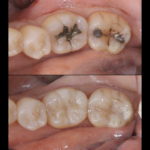

痛くない虫歯・・?

こんにちは!院長の渡辺です。 本格的な寒波がきていますが体調崩されたりしてないでしょうか? 風邪をひくと咳や熱がでますね、転んで擦りむくと痛みや血がでます。 虫歯はどうでしょう?冷たいものがしみたり、ずきずきしたりといった症状があればわかりやすいですが。。 実は無症状に進む虫歯もあります。 特に大人は歯の中にある神経が子供に比べると細いので痛みがですそのままじわじわと進行していくことも珍しくありま...